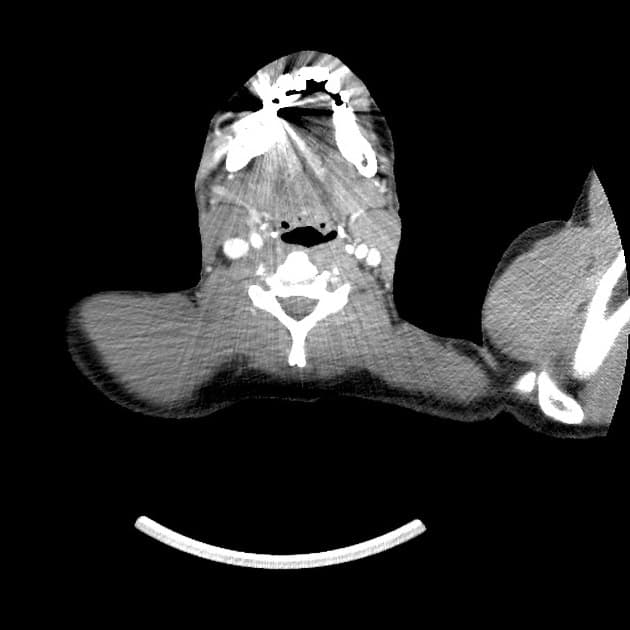

- 1.Vết rách gan kèm máu tụ dưới vỏ

- 2.Tổn thương nhu mô gan với thoát thuốc cản quang hoạt động

- "Hệ thống phân độ chấn thương gan AAST 2018 kết hợp cả dạng tổn thương hình thái và mức độ liên quan mạch máu để phân loại chính xác hơn."

- "Độ I–III biểu hiện các vết rách hoặc máu tụ ngoại biên, trong khi độ IV–V liên quan tổn thương nhu mô trung tâm hoặc chấn thương mạch máu lớn."